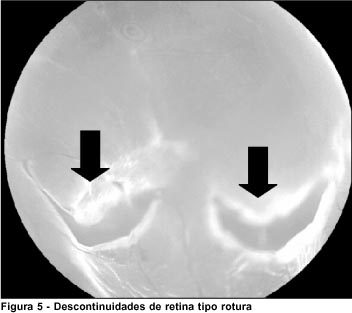

As roturas (Figura 5) estão associadas ao descolamento regmatogênico de retina nas baixas miopias 4. A prevalência dessas alterações nos pacientes desta pesquisa (4,3%) foi próxima à mencionada por Byer 25(8,7%) e registrada por Foos 11 (1,9%) em grandes amostras de necropsia.

A incidência de roturas varia com a idade, sendo maior na 4ª, 5ª e 6ª décadas de vida 16, 26-27, o que permite esperar um aumento do número de roturas nos pacientes deste estudo com o passar dos anos. Portanto, o acompanhamento desses pacientes no pós-operatório é importante, bem como observar novas roturas e sua eventual relação com procedimentos a que foram submetidos.

Neste estudo as roturas de retina foram observadas em menor número nos olhos com miopia moderada, sendo a prevalência 2,4 vezes maior nas miopias baixas e três vezes maior nas miopias altas. O mesmo foi observado no trabalho de Pierro et al.28, em que relacionaram apenas pacientes míopes, encontrando maior prevalência de roturas nas miopias baixas e altas 29.

Byer em estudo de 223 olhos com roturas retinianas e buracos com ou sem opérculo em pacientes fácicos, assintomáticos e sem outra degeneração retiniana associada, observou que nenhum deles desenvolveu descolamento regmatogênico de retina por aproximadamente sete anos e meio 16. Neste trabalho, o grupo com roturas de retina apresentou as mesmas características dos critérios de elegibilidade usados no trabalho de Byer (1982) o que leva a acreditar que estes pacientes apresentem chance pequena de desenvolver descolamento regmatogênico de retina.